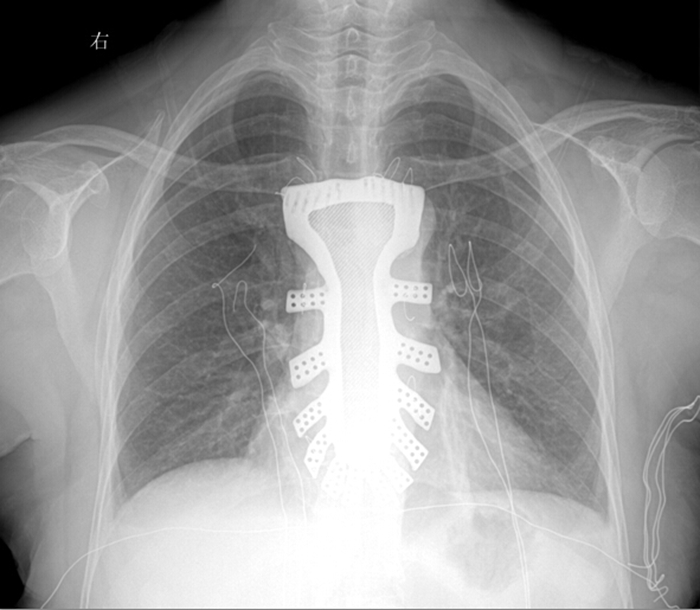

“手术历时2.5小时,对患者的胸骨进行了整体切除,置换了钛合金胸骨,目前患者恢复良好,未发现任何并发症。”王小平教授称,根据专业机构检索,该手术是世界首例针对胸骨肿瘤疾病,将3D打印的可植入性钛合金胸骨植入人体,实现病变胸骨的整体置换的手术。该手术的成功意味着未来将会为更多的胸骨肿瘤患者带来福音。

据王小平教授介绍,唐都医院3D打印小组经过精密计算患者胸骨的大小、形状等,充分研究讨论,历时一周,为患者设计出了手术使用的3D胸骨模型,并与西北工业大学凝固技术国家重点实验室合作,为患者打印出了1:1钛合金胸骨模型。随后,又对该模型进行了一系列严密的医学处理。